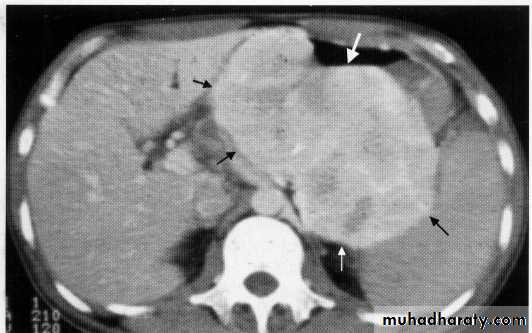

Hepatoma + met.

Early cirrhosis + budd chiari

Met. adenocarcinoma